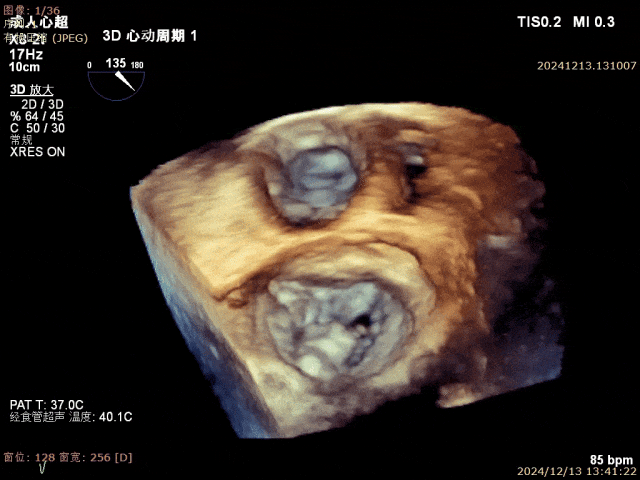

患者为68岁男性,3月前出现气短,活动后明显,休息可缓解,无明显胸痛,无夜间呼吸困难,就诊当地医院考虑“肺炎、心衰”,给予对症治疗好转,具体不详,无明显发热,无咳嗽咳痰,出院后未规律服药。10天前,气短再发,就诊当地医院心脏彩超提示二尖瓣后叶腱索断裂,二尖瓣关闭不全伴重度反流。左心增大,室间隔增厚,肺动脉高压,三尖瓣轻度反流,主动脉瓣中度反流。心电图提示房颤,左室肥大。为进一步诊治入院。经食道超声提示:患者二尖瓣后叶脱垂伴腱索断裂,前叶2.6cm,后叶1.4cm,脱垂宽度16mm,脱垂高度8mm,瓣口面积6.0cm²。

术前影像